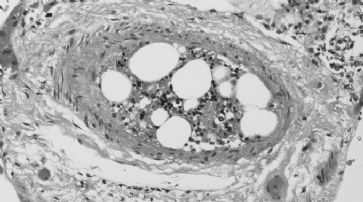

Neue Knochenmark-Transplantationsmethode getestet

London - Ärzte am Great Ormond Street Hospital haben ein neues Verfahren zur Transplantation von Knochenmark durchgeführt.

Laut dem leitenden Wissenschaftler Waseem Qasim könnte dieses Verfahren helfen, Engpässe bei Spendern zu lindern, da keine perfekte Übereinstimmung erforderlich ist. Fünf Jahre alter Junge behandelt

Der Patient Mohammed Ahmed ist jetzt fast fünf Jahre alt. Er war eines von den ersten drei Kindern weltweit, bei denen das neue Verfahren eingesetzt wurde. Der Junge leidet an einem schweren kombinierten Immunschwäche-Syndrom und wartete seit Jahren auf einen geeigneten Spender. Das Kind wurde mit einem Jahr zur Behandlung an dieses Krankenhaus überwiesen.

Das schwache Immunsystem macht den Jungen anfälliger für Infektionen. Eine Transplantation des Knochenmarks ist derzeit die einzige bekannte Behandlungsmöglichkeit. Während der Patient auf der Warteliste stand, erkrankte er schwer an einer Schweinegrippe. Die Ärzte entschieden daher, dass seine einzige wirkliche Chance eine Transplantation mit einem Knochenmark ist, das nicht genau mit dem seinen übereinstimmt. Der Vater stellte sich als Spender zur Verfügung und stimmte auch der Behandlung seines Sohnes zu.

Sicherheitsschalter verhindert Abstossung

Vor der Knochenmarksspende wurde der Vater gegen Schweinegrippe geimpft, damit seine Knochenmarkszellen lernen konnten diese Krankheit zu bekämpfen.

Kinder, für die kein perfekter Spender zur Verfügung steht, können die gleichen Heilungschancen haben.(Symbolbild) /

Die gespendeten Immunzellen wurden von den Ärzten mit einem Sicherheitsschalter versehen, der bei den T-Zellen die Selbstzerstörung einleiten würde, sollte der Körper des Patienten sie abstossen. Eine Abstossung oder "Graft-versus-Host Disease" gilt bei einer Knochenmarkstransplantation als schwere Komplikation und grosse medizinische Herausforderung.

Die 2011 durchgeführte Transplantation war aber erfolgreich. Der Sicherheitsschalter musste nicht aktiviert werden. Mohammed muss zwar immer noch eine Reihe von Medikamenten einnehmen, sein Immunsystem ist aber heute in einem besseren Zustand. Laut Qasim könnte der neue Behandlungsansatz bedeuten, dass Kinder, für die kein perfekter Spender zur Verfügung steht, die gleichen Heilungschancen haben können. "Wir gehen davon aus, dass Mohammed von seiner Krankheit geheilt ist. Er sollte jetzt ein ziemlich normales Leben führen können."

Tausende warten auf geeignete Spender

Details der Behandlung des Patienten und der vom Krankenhaus, dem King's College London und dem Institute of Child Health, wurden im Fachmagazin PLoS One veröffentlicht. Derzeit warten allein in Grossbritannien rund 1600 Patienten auf eine Knochenmarkspende. Weltweit sind 37'000 Menschen betroffen. Nur 30 Prozent von ihnen finden innerhalb ihrer Familien einen passenden Spender.